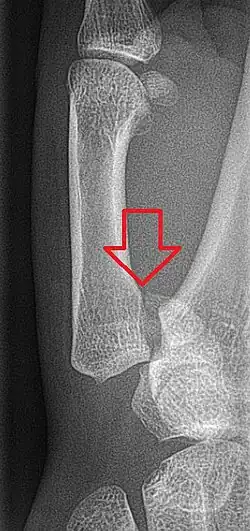

Bennett's fracture on x-ray

Bennett's fracture or Bennett fracture is a type of partial broken finger involving the base of the thumb, and extends into the carpometacarpal (CMC) joint.[1]

This intra-articular fracture is the most common type of fracture of the thumb, and is nearly always accompanied by some degree of subluxation or frank dislocation of the carpometacarpal joint.